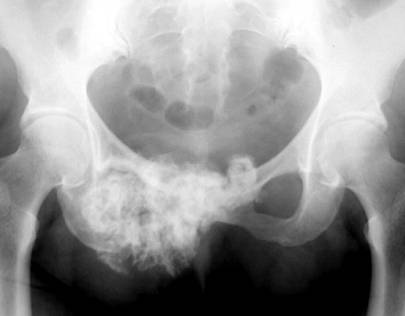

Chondrosarcoma